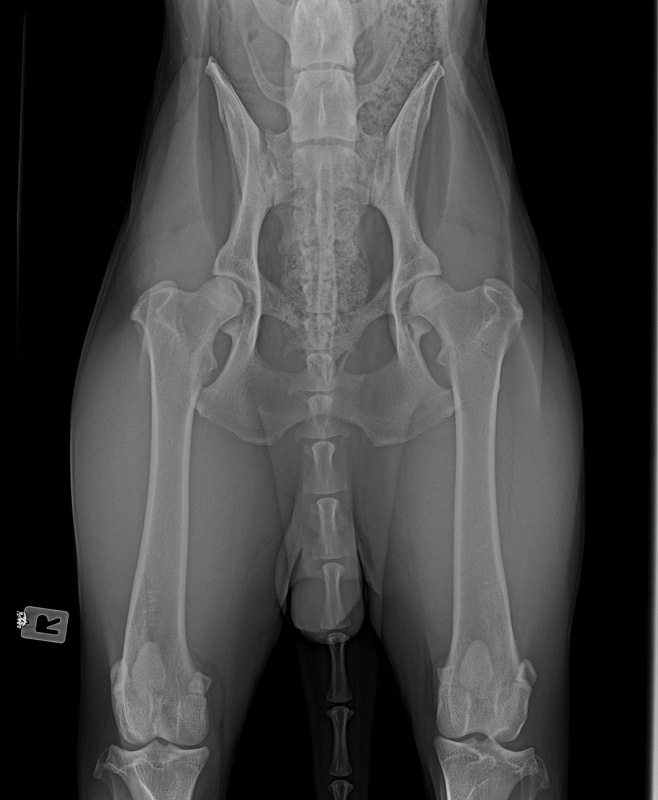

Wir warten jetzt mal die offizielle Auswertung ab. Bin auch gespannt, was nun bei OCD und Lendenübergangswirbel rauskommt. Und welcher LÜW-Typ.

Das ist ganz einfach. Man schreibt ne Email, bittet um ein Privatgutachten und schickt ihm die Röntgenbilder.

Das Ergebnis + Rechnung kommt echt schnell ( 1-2 Tage)